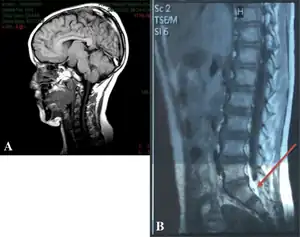

Currently, clinical diagnosis is through a brain MRI and genetic sequencing for GLI 13 gene, which is known to cause Pallister-Hall Syndrome, as well as Greig cephalopolysyndactyly syndrome. Genetic testing can find and identify the corresponding disorder.[9]